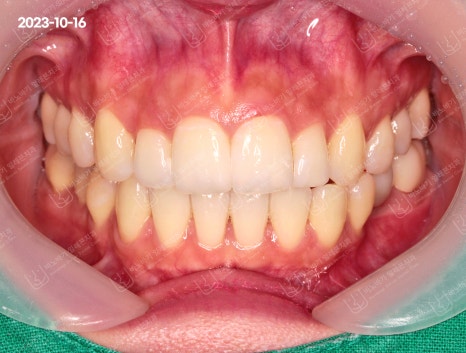

튀어나온 입술이 들어갔습니다. 심미선 안쪽으로 위치하게 되어 이상적인 안모가 완성되었네요. 세련된 인상으로 바뀌셨습니다.

다만 전체 치열의 후방이동과 전치부의 각도를 재조정하면서 외모적 측면에 있어 이상적인 좋은 결과를 이끌어냈습니다.

임플란트도 잘 완성되었습니다. 외관상으로도 심미적인데다가 기존 어금니의 저작기능까지 수행할 수 있게 만들었습니다.

앞니도 좀 더 말끔해졌습니다. 덧니 때문에 겹쳐졌던 곳이 가지런한 모습으로 정리됐고, 중심선까지 일치시켰습니다.

그러면서 구강 내 위생관리도 예전보다 더 수월해졌습니다. 기능적인 단점이 해결됐네요.

악궁 모양도 좀 더 이상적인 U자형 아치로 완성됐습니다. 추가적인 조치를 요하지 않아 고정성 유지장치를 부착하여 교정을 마무리하였습니다.